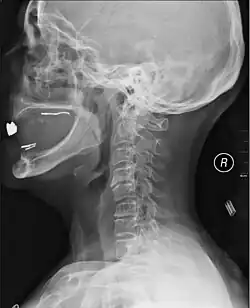

K vyšetření a nalezení postižené lokace se užívá nejčastěji rentgenu, pro složitější případy pak také CT a MRI.